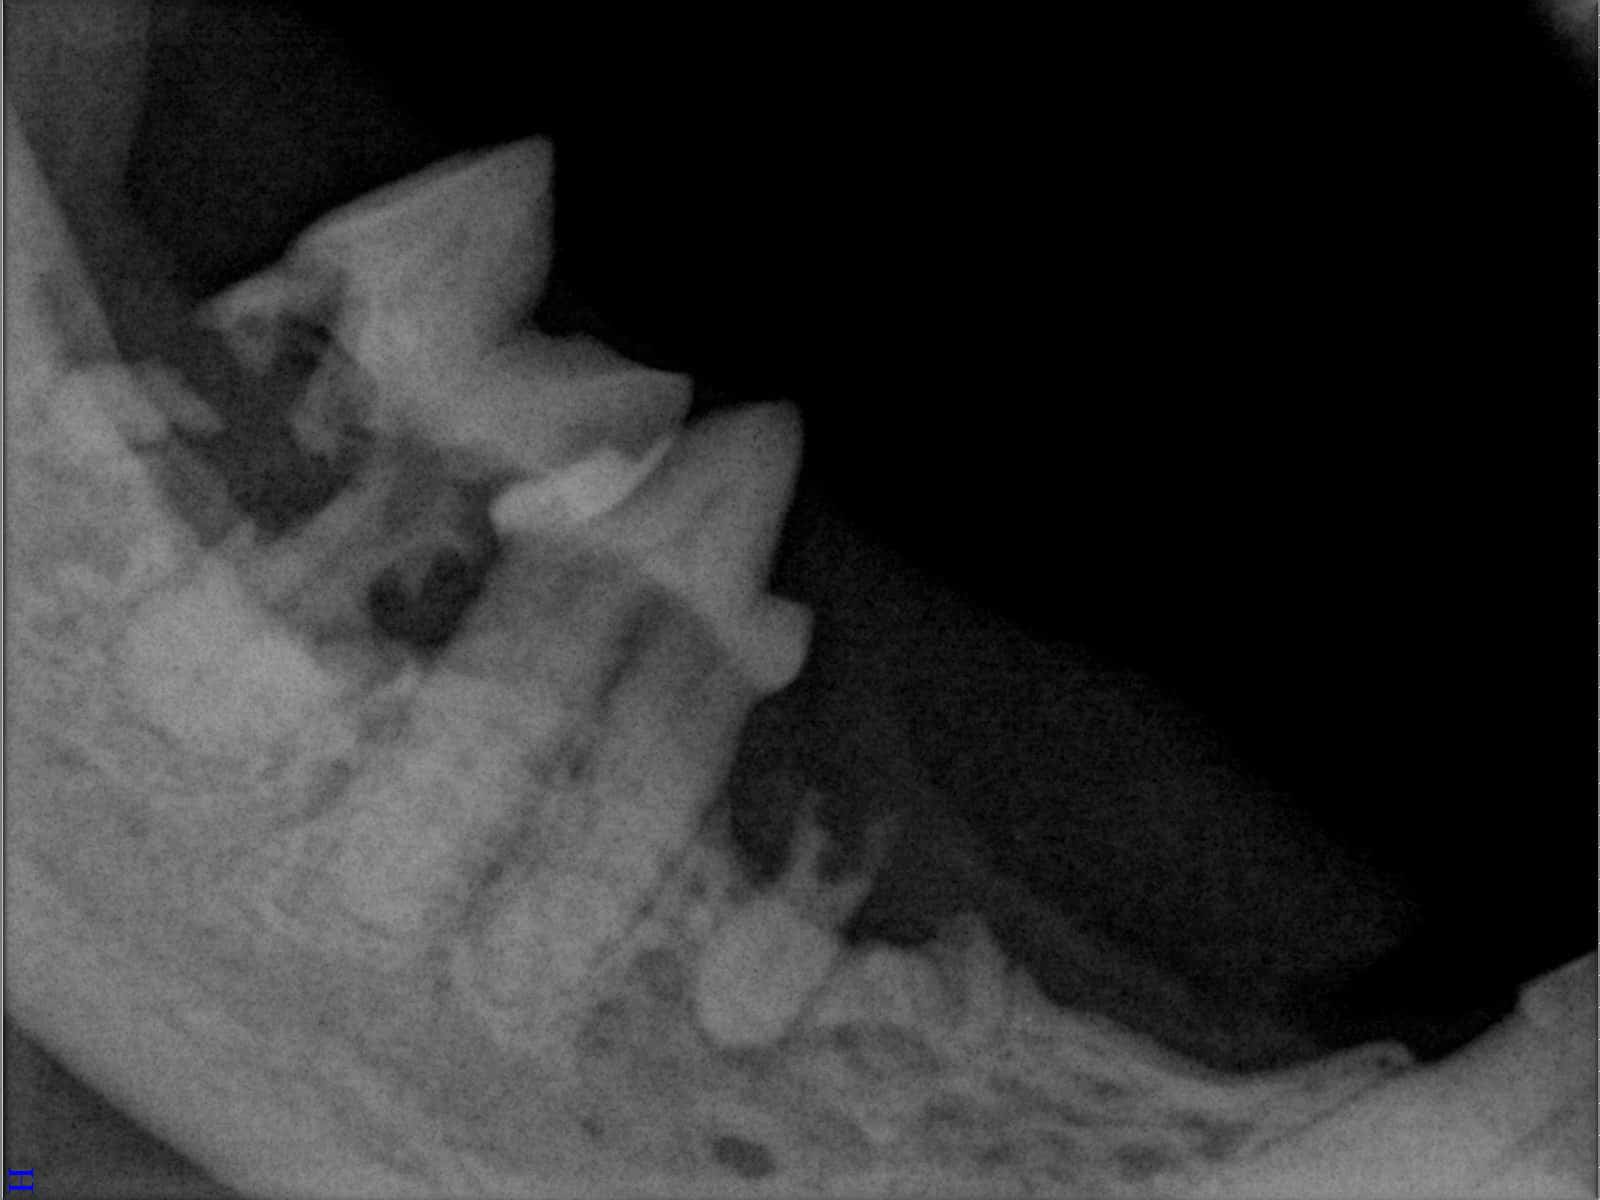

Ein entscheidender Baustein der FORL-Diagnostik ist das dentale Röntgen. Viele Läsionen sind von außen nicht sichtbar und lassen sich ausschließlich mithilfe moderner Röntgentechnik erkennen. In der Hamburger Praxis kommt digitales Dentalröntgen zum Einsatz, das detailreiche Aufnahmen bei geringer Strahlenbelastung ermöglicht. So kann FORL bereits in frühen Stadien diagnostiziert werden.

Das sehen Sie von außen – so sieht es auf den Röntgenbildern aus.

FORL Katze Röntgenbild

Röntgenbilder